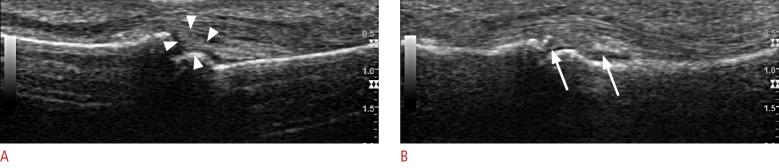

The recent development of advanced high-resolution transducers has enabled the fast, easy, and dynamic ultrasonographic evaluation of small, superficial structures such as the finger. In order to best exploit these advances, it is important to understand the normal anatomy and the basic pathologies of the finger, as exemplified by the following conditions involving the dorsal, volar, and lateral sections of the finger: sagittal band injuries, mallet finger, and Boutonnière deformity (dorsal aspect); flexor tendon tears, trigger finger, and volar plate injuries (volar aspect); gamekeeper's thumb (Stener lesions) and other collateral ligament tears (lateral aspect); and other lesions. This review provides a basis for understanding the ultrasonography of the finger and will therefore be useful for radiologists.

先进的高分辨率换能器的最新发展使得对手指等小而浅表结构进行快速、简便和动态的超声评估成为可能。为了充分利用这些进展,了解手指的正常解剖结构和基本病变非常重要,以下列举了累及手指背侧、掌侧和侧方的一些情况,包括:矢状带损伤、锤状指和纽扣畸形(背侧);屈肌腱撕裂、扳机指和掌板损伤(掌侧);守猎者拇指(斯滕纳损伤)和其他侧副韧带撕裂(外侧);以及其他病变。这篇综述为理解手指的超声检查提供了基础,因此对放射科医生非常有用。